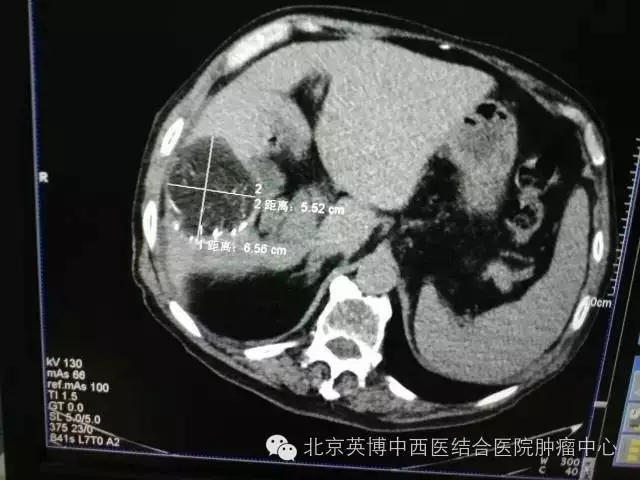

一位82岁的高龄男性,在4月的例行体检中发现肝占位,并于7月份在市内其他医院确诊,后进行过介入治疗一次、放疗25次。因其本人也在医疗系统工作几十年,对于现今的治疗技术和手段的关注度、敏锐度高于常人,当获悉北京英博中西医结合医院特邀原中国医学科学院肿瘤医院原副院长刘伯齐教授亲自来医院开展氩氦刀手术后,慕名治疗,术后效果也确实如他所期,非常明显,未出现任何不良反应。